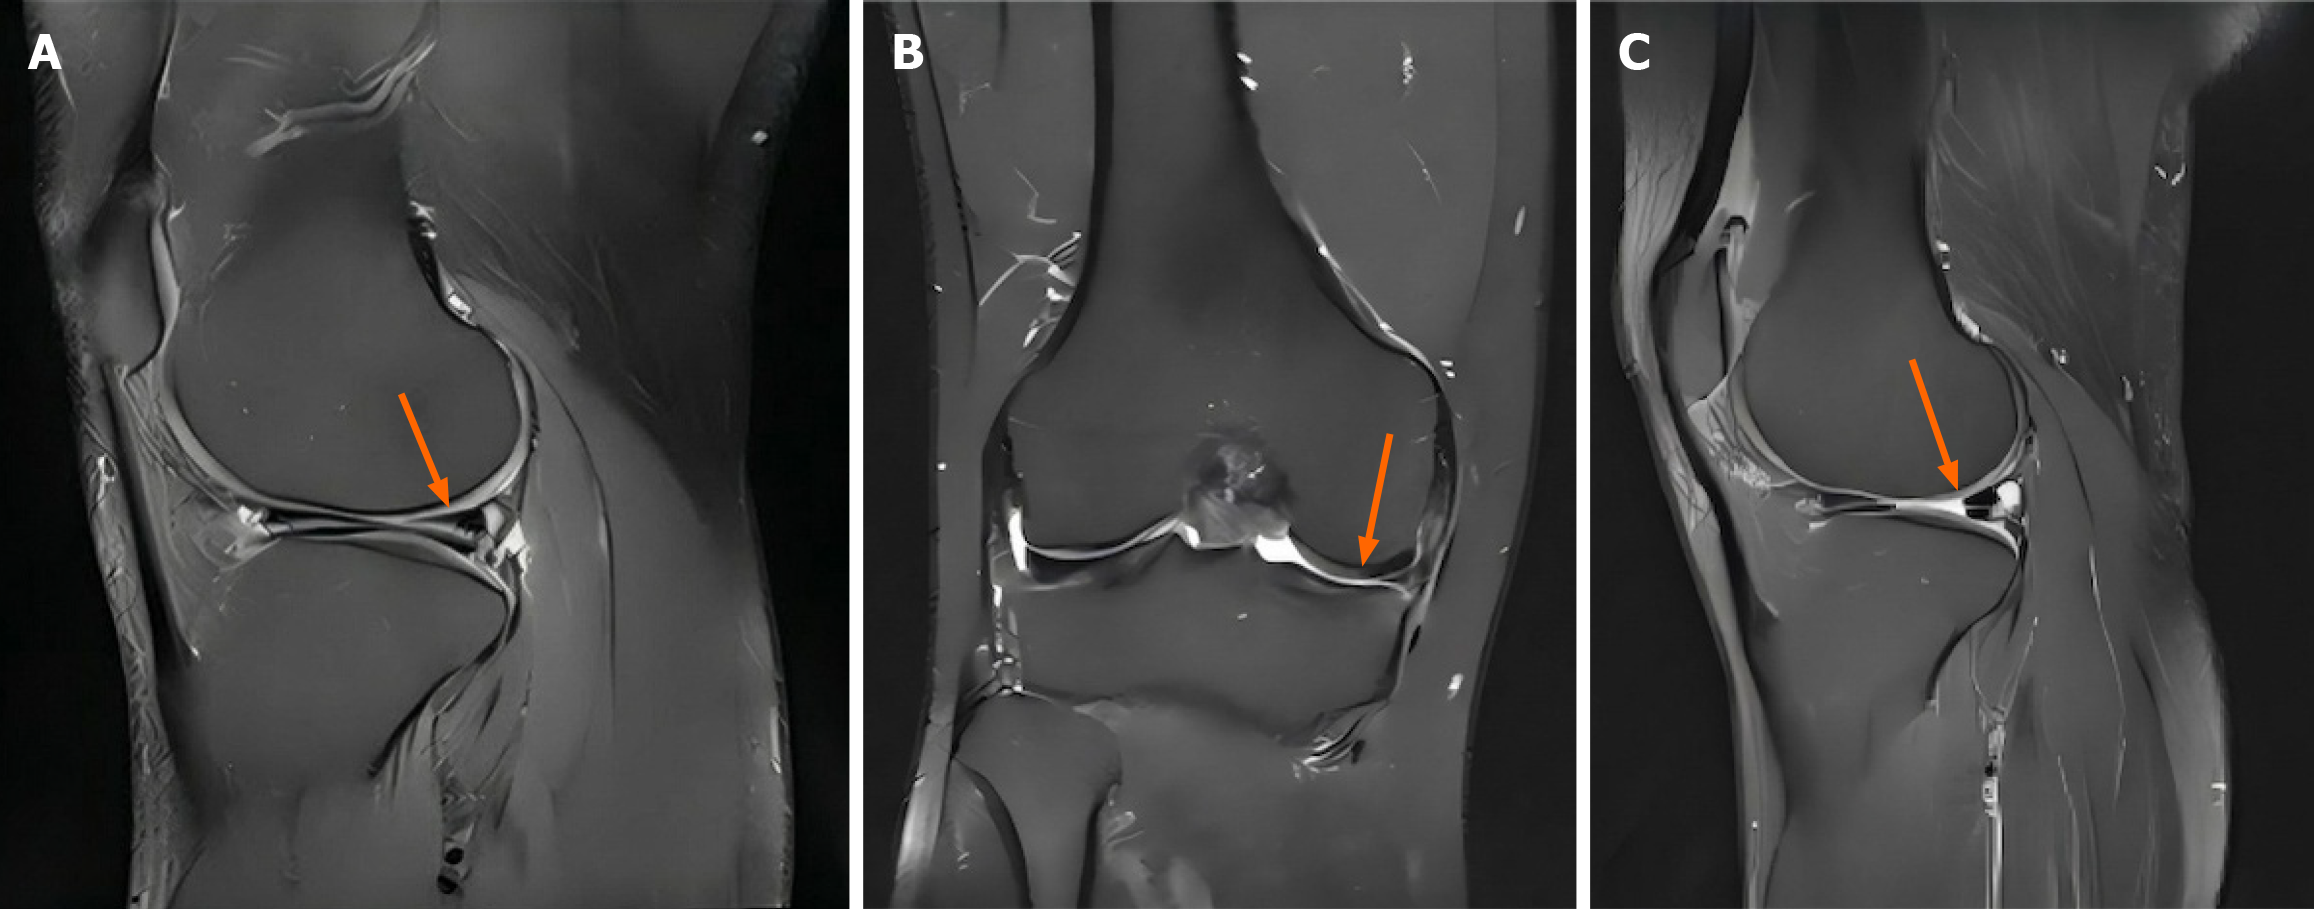

圖2:間充質(zhì)干細胞治療后半月板組織的代表性磁共振成像圖像。

A:治療前矢狀位T2加權(quán)像顯示內(nèi)側(cè)半月板后角高信號強度(箭頭),提示III級退行性改變;B:治療前冠狀位T2加權(quán)像顯示內(nèi)側(cè)半月板實質(zhì)內(nèi)信號異常(箭頭);C:治療后(12個月)矢狀位T2加權(quán)像顯示后角信號強度降低(箭頭)且組織均勻性改善。